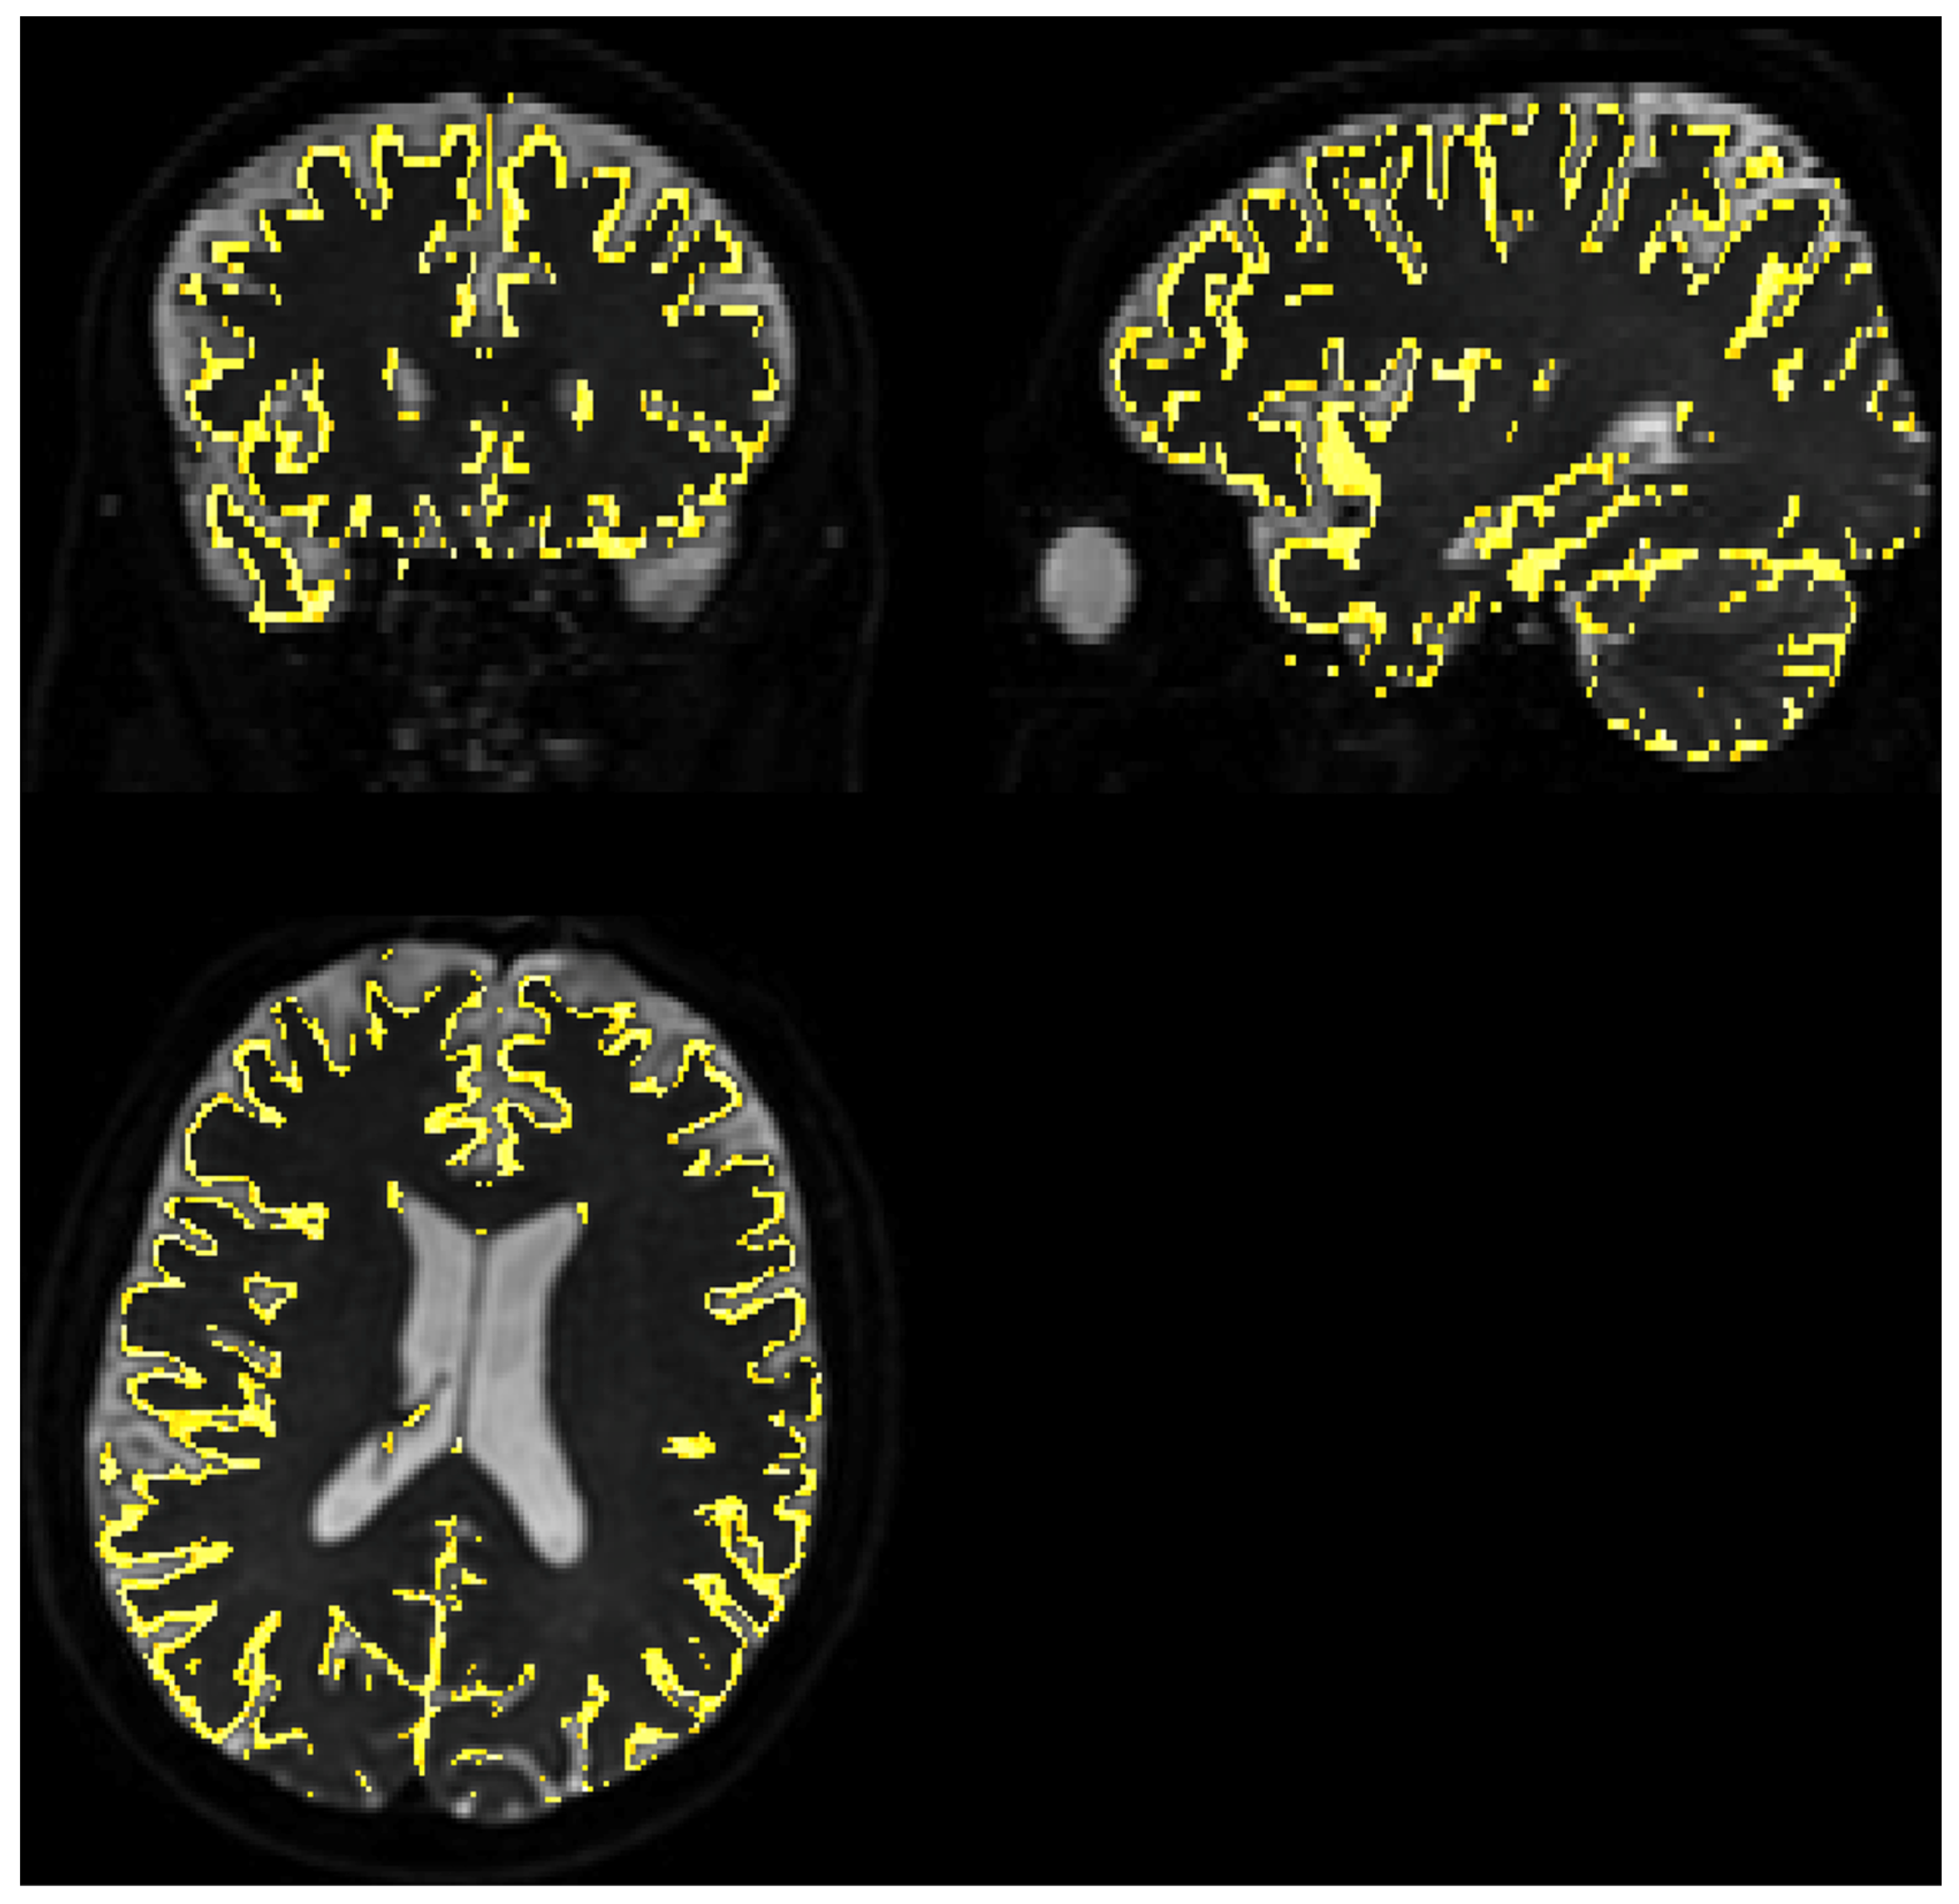

The SNR level was separately estimated for WM and GM voxels using FSL FAST segmentation with Tissue Probability Maps (TPMs). Acquiring high-resolution T2 data allowed for the precise separation of these two tissue types. The results were comparable to whole brain analysis and to each other. Estimated parameters for WM, based on 210,523 voxels, were as follows: average = 21.56, median = 21.23, minimum = 1.36, and maximum = 62.14. For GM, mask depicted on Figure 3, based on 68,067 voxels average = 20.69, median = 20.32, minimum = 1.25, and maximum = 117.77.

Figure 3.

Gray matter coverage on DWI scan. The yellow shape represents the coverage of the gray matter map with a probability > 80% overlayed on image, regridded to IVIM DWI resolution.